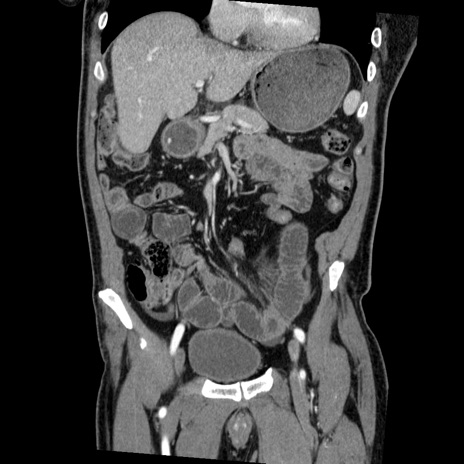

症例22(冠状断像)

【症例】50歳代男性

【主訴】腹痛

【現病歴】AVMからの被殻出血のため回復期リハ病棟入院中。 本日午後3時頃急に下腹部痛が出現した。

【既往歴】AVM、被殻出血、虫垂炎、高血圧

【身体所見】意識晴明、左半身不全麻痺、会話の理解は良好、36.5°C、腹部:膨隆、全体に板状硬、下腹部正中に圧痛点あり、反跳痛-、筋性防御不明、右下腹部にope scar

【データ】WBC 9400、CRP 0.06